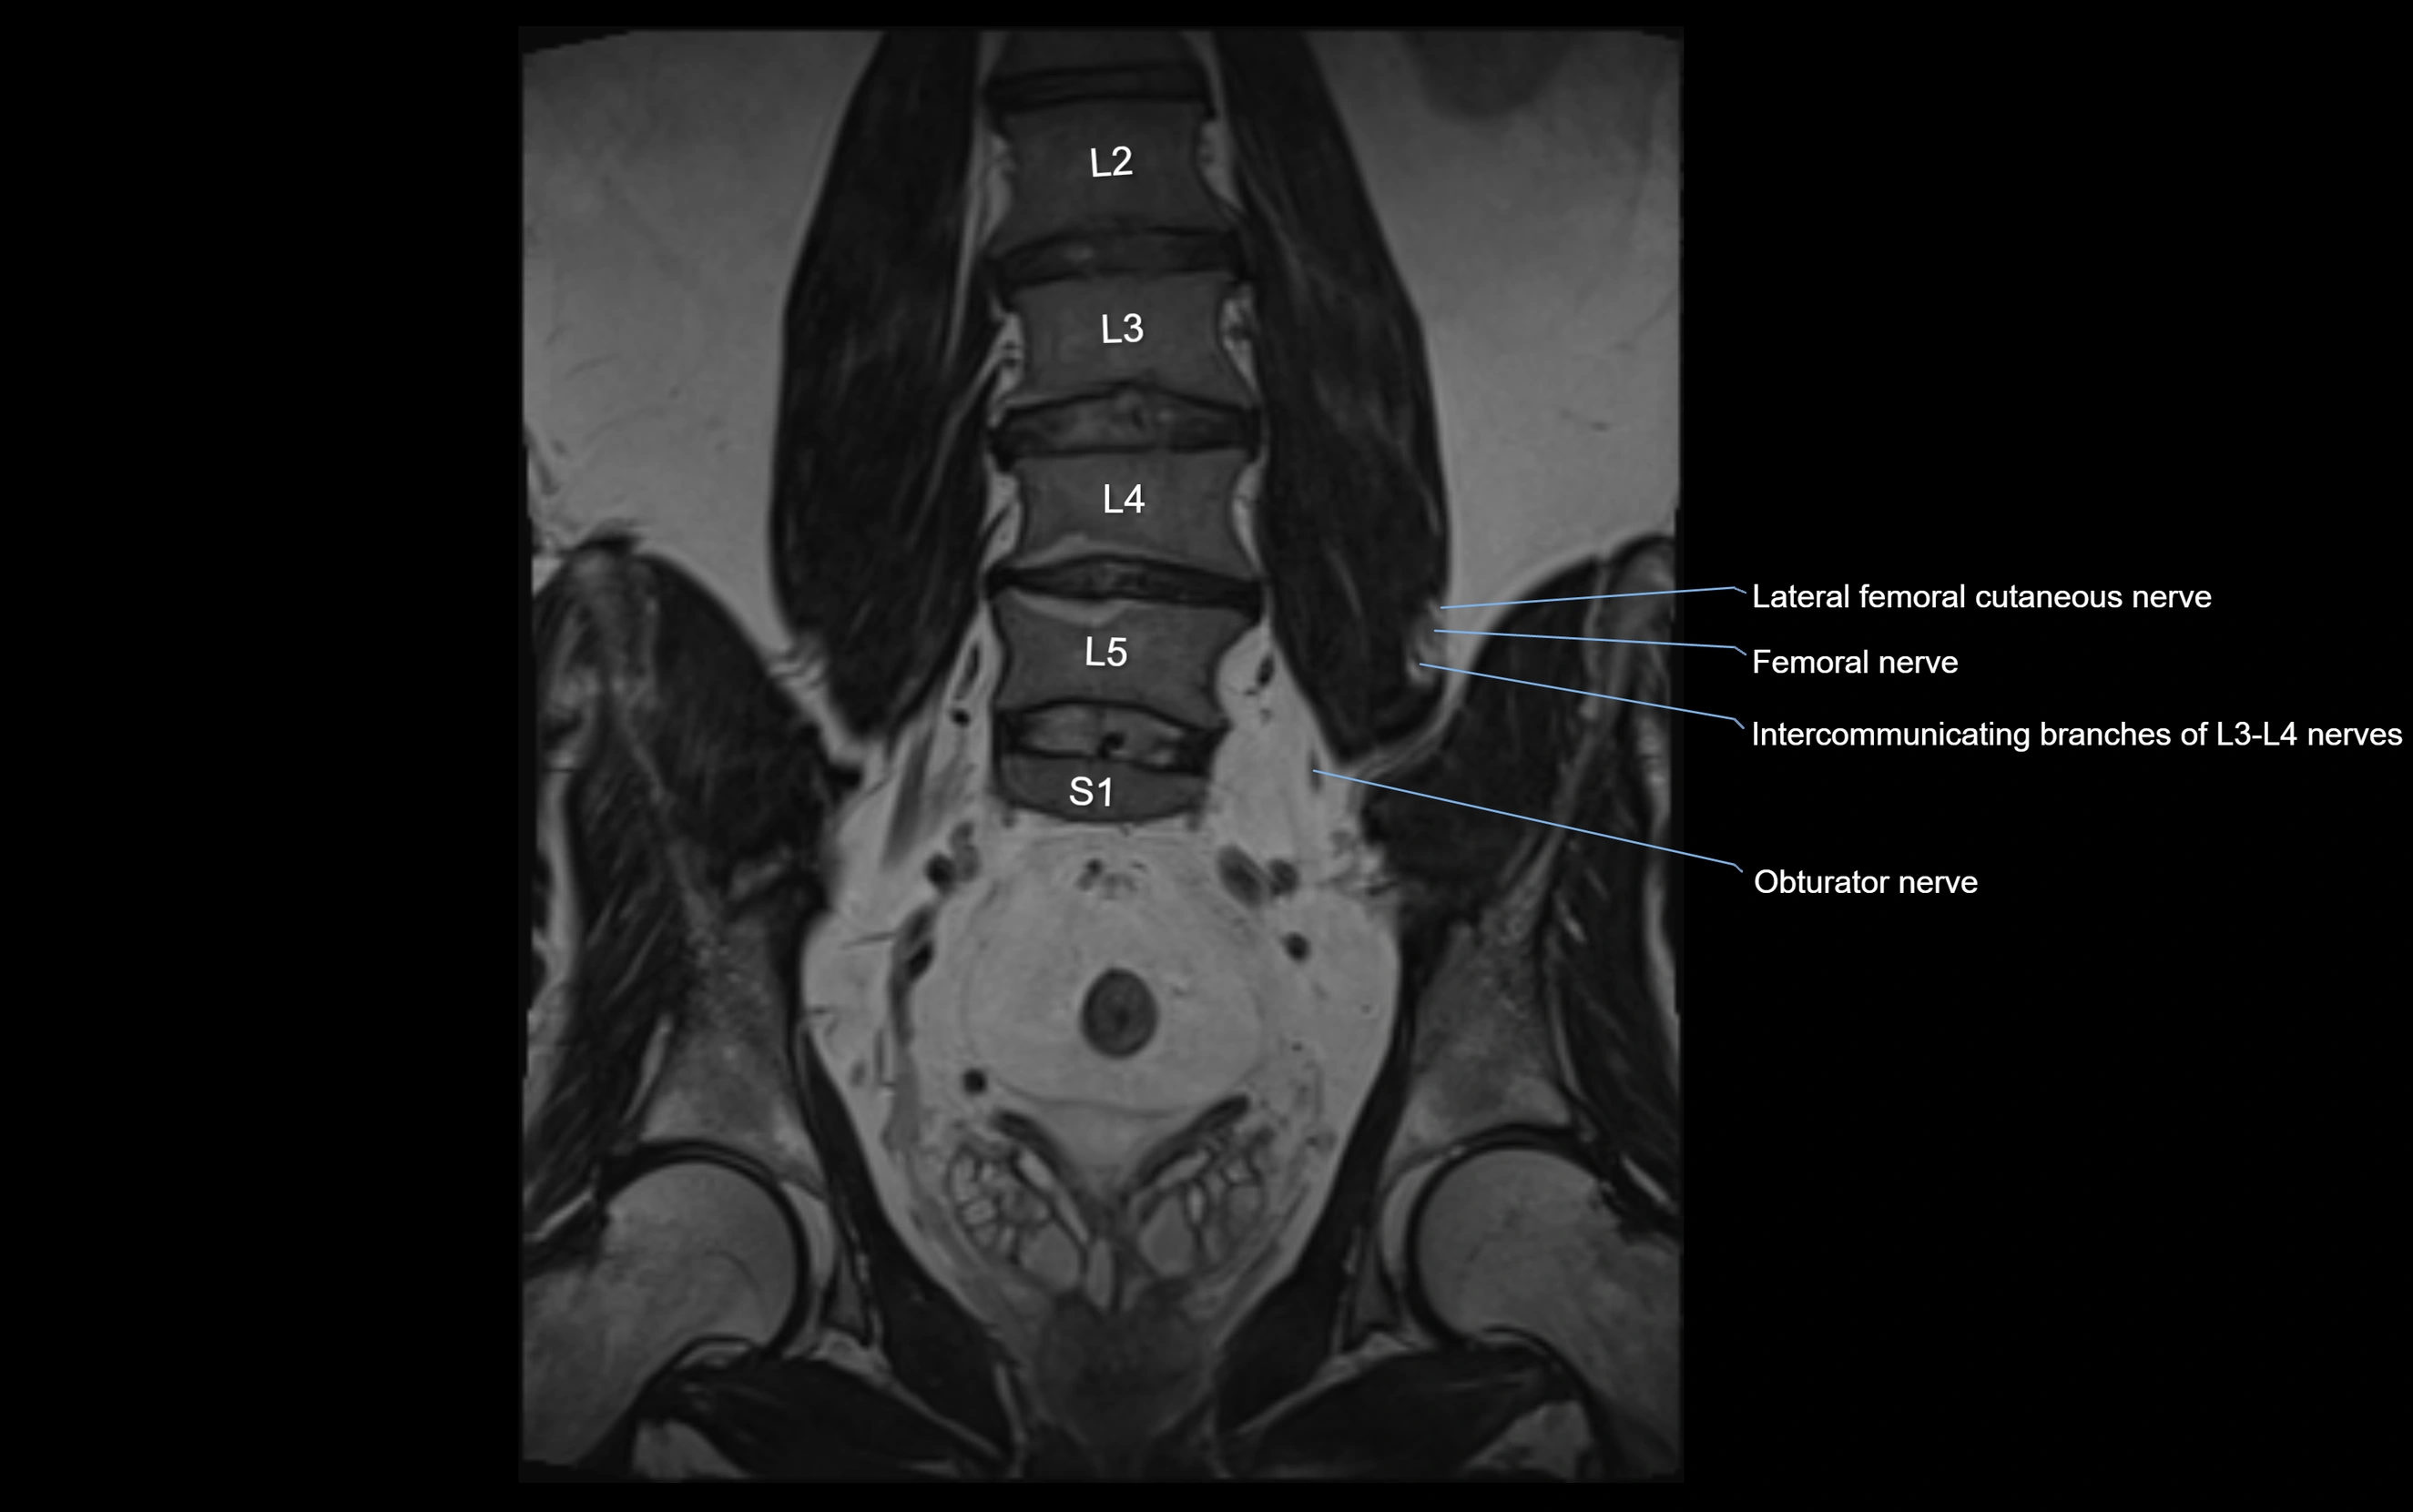

MRI Appearance

T1-weighted images:

• Nerve appears as a very thin low-to-intermediate signal intensity structure

• Surrounded by bright fat, aiding visualization

T2-weighted images:

• Nerve shows intermediate to mildly hyperintense signal compared to muscle

• Pathological involvement appears brighter

STIR (Short Tau Inversion Recovery):

• Normal nerve appears dark

• Inflamed or entrapped nerve appears bright hyperintense

T1 Fat-Sat Post-Contrast:

• Normal nerve enhances minimally

• Pathologic nerve (neuritis, entrapment, tumor infiltration) shows focal or diffuse enhancement

3D T2 SPACE / CISS:

• Nerve appears intermediate to mildly hyperintense compared to muscle

• Surrounded by bright fat or CSF, improving visualization

• Best sequence for mapping small pelvic nerves such as the anococcygeal